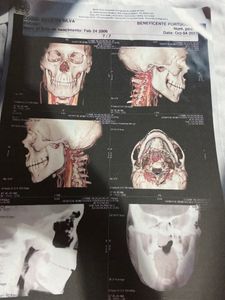

Esse é o Cosme ele tem 15 anos e tem um Angiofibroma nasofaríngeo que é um tumor benigno na cabeça que cresce constantemente e está em um estado muito delicado o Cosme precisa fazer a cirurgia em um hospital especializado em São Paulo e está a 3 meses na espera internado no hospital Ophir Loiola em Belém do Pará , precisamos arrecadar dinheiro para os gastos dele e da minha mãe com necessidades básicas tanto pra agora como depois que eles conseguirem o leito em São Paulo e ele for transferido .